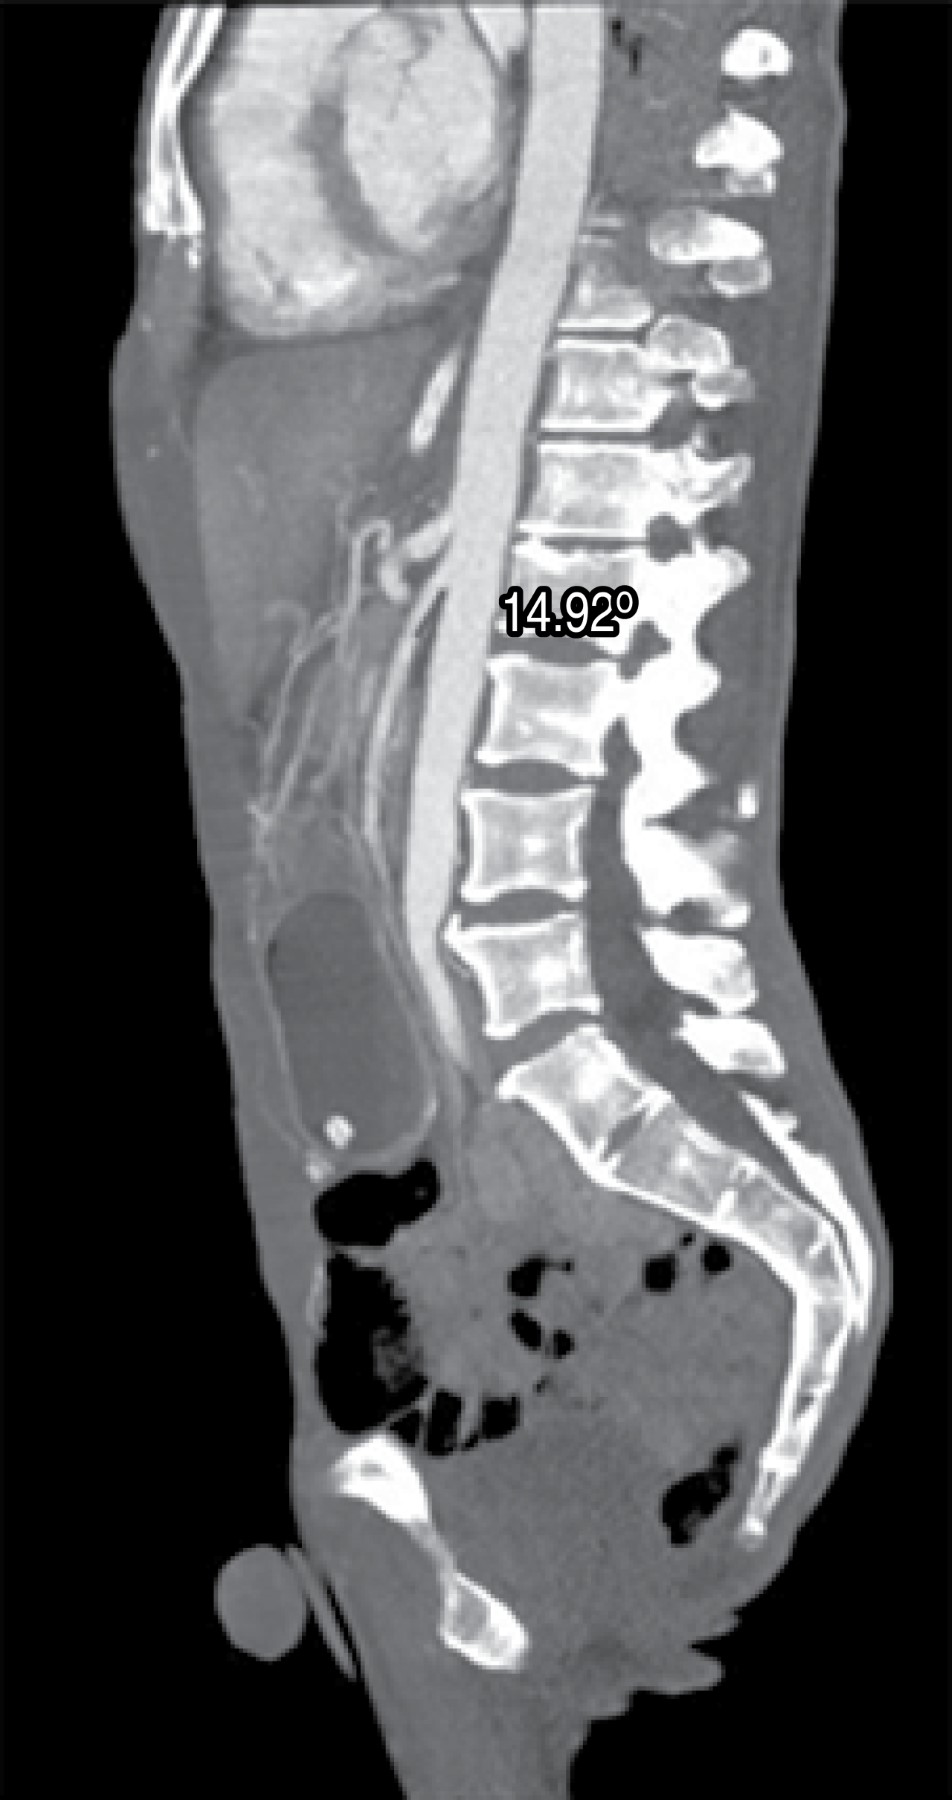

Diagnostic studies require a high index of suspicion since symptoms may be nonspecific. Diagnostic imaging criteria include: 1) Duodenal obstruction with an abrupt cut in the third portion. 2) Aortomesenteric angle less than 25o (considered the most sensitive measure of the diagnosis). 3) Aortomesenteric distance less than 8 mm. 4) High fixation of the duodenum by the ligament of Treitz.8

An abdominal CT scan was performed in which gastric dilatation was identified with loss of gastric folds and decreased distance between the aorta and superior mesenteric artery, measuring 8.05 mm (Figure 1). The sagittal section of the CT scan showed an acute aortomesenteric angle of 14.92o (Figure 2). Since his admission, he received management with gastric decompression through a nasogastric tube, water and electrolyte replacement, analgesics, and antibiotic therapy with a third-generation cephalosporin antibiotic; however, the obstruction persisted despite conservative management for 48 hours, so surgical management was proposed and accepted. A laparoscopic approach with five ports was performed; the transverse colon was mobilized, and the site of obstruction was seen as secondary to clamping of the superior mesenteric artery between the third and fourth portion of the duodenum. A mechanical duodenojejunal-anastomosis was performed at 60 cm from the ligament of Treitz; the gastroenterostomy was closed in two planes with slow absorption monofilament suture for the first plane and non-absorbable for the second one. Postoperative evolution was good. He started drinking liquids at 24 hours and progressed to a soft diet at 48 hours. He was discharged home due to improvement 48 hours after the procedure. There have not been any subsequent clinical sequelae after two months. He has had adequate tolerance to the oral route, but the patient has not attended to control for post-surgical follow-up.

Figure 2